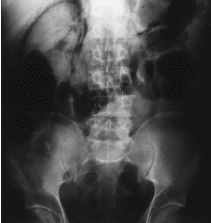

En la exploración física destacaban dolor a la palpación en FII y enfisema subcutáneo más pronunciado en hemiabdomen derecho. En la serie radiológica se incluyó: radiografía de abdomen (fig. 1) y de tórax (fig. 2) así como tomografía computarizada abdominal con ventana normal (fig. 3) y ventana modificada (fig. 4), evidenciándose retroneumoperitoneo bilateral con extensión a partes blandas (región del cuello).

Fig. 4.